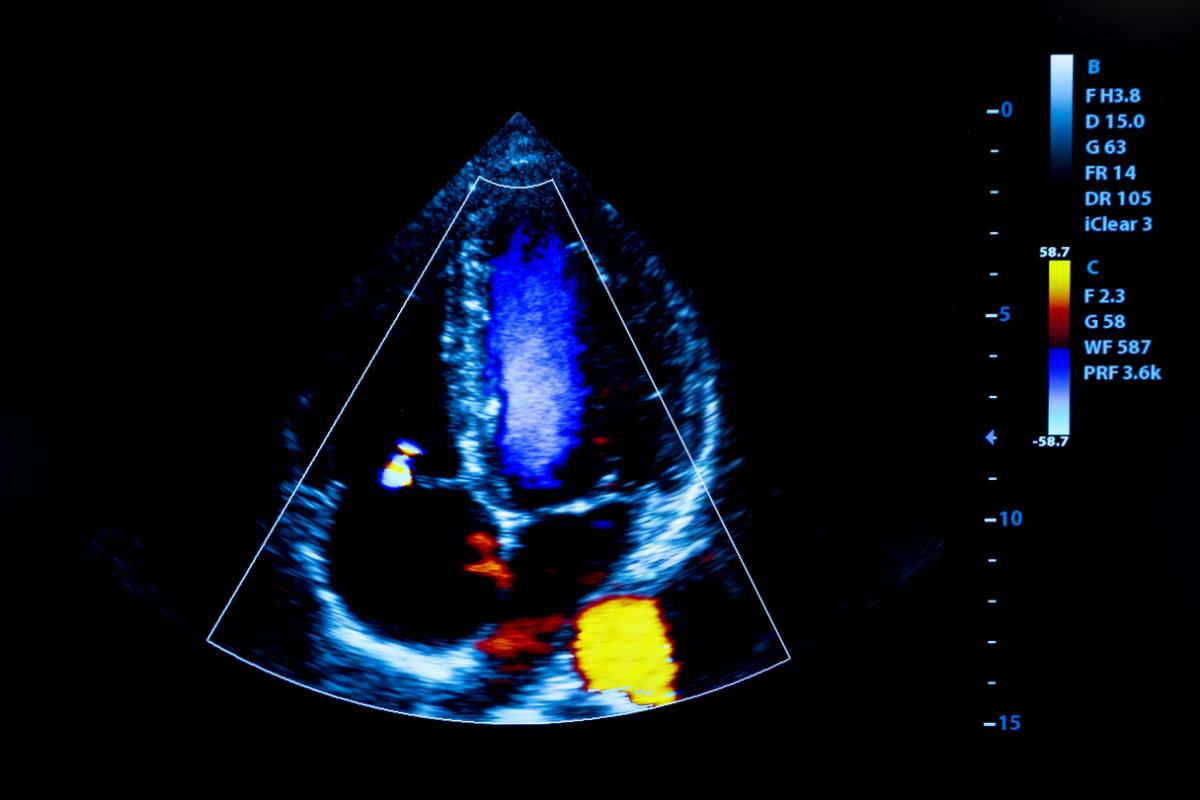

心エコー検査について

「胸の痛みや息苦しさ、動悸、不整脈などの症状がある場合には、心エコー検査(心臓超音波検査)を行います。

超音波を用いて心臓の大きさや動き、弁の状態などを確認することで、心疾患や胸部の異常を早期に見つけることができます。

放射線を使わないため身体への負担が少なく、妊娠中の方や高齢の方でも安心して受けていただけます。